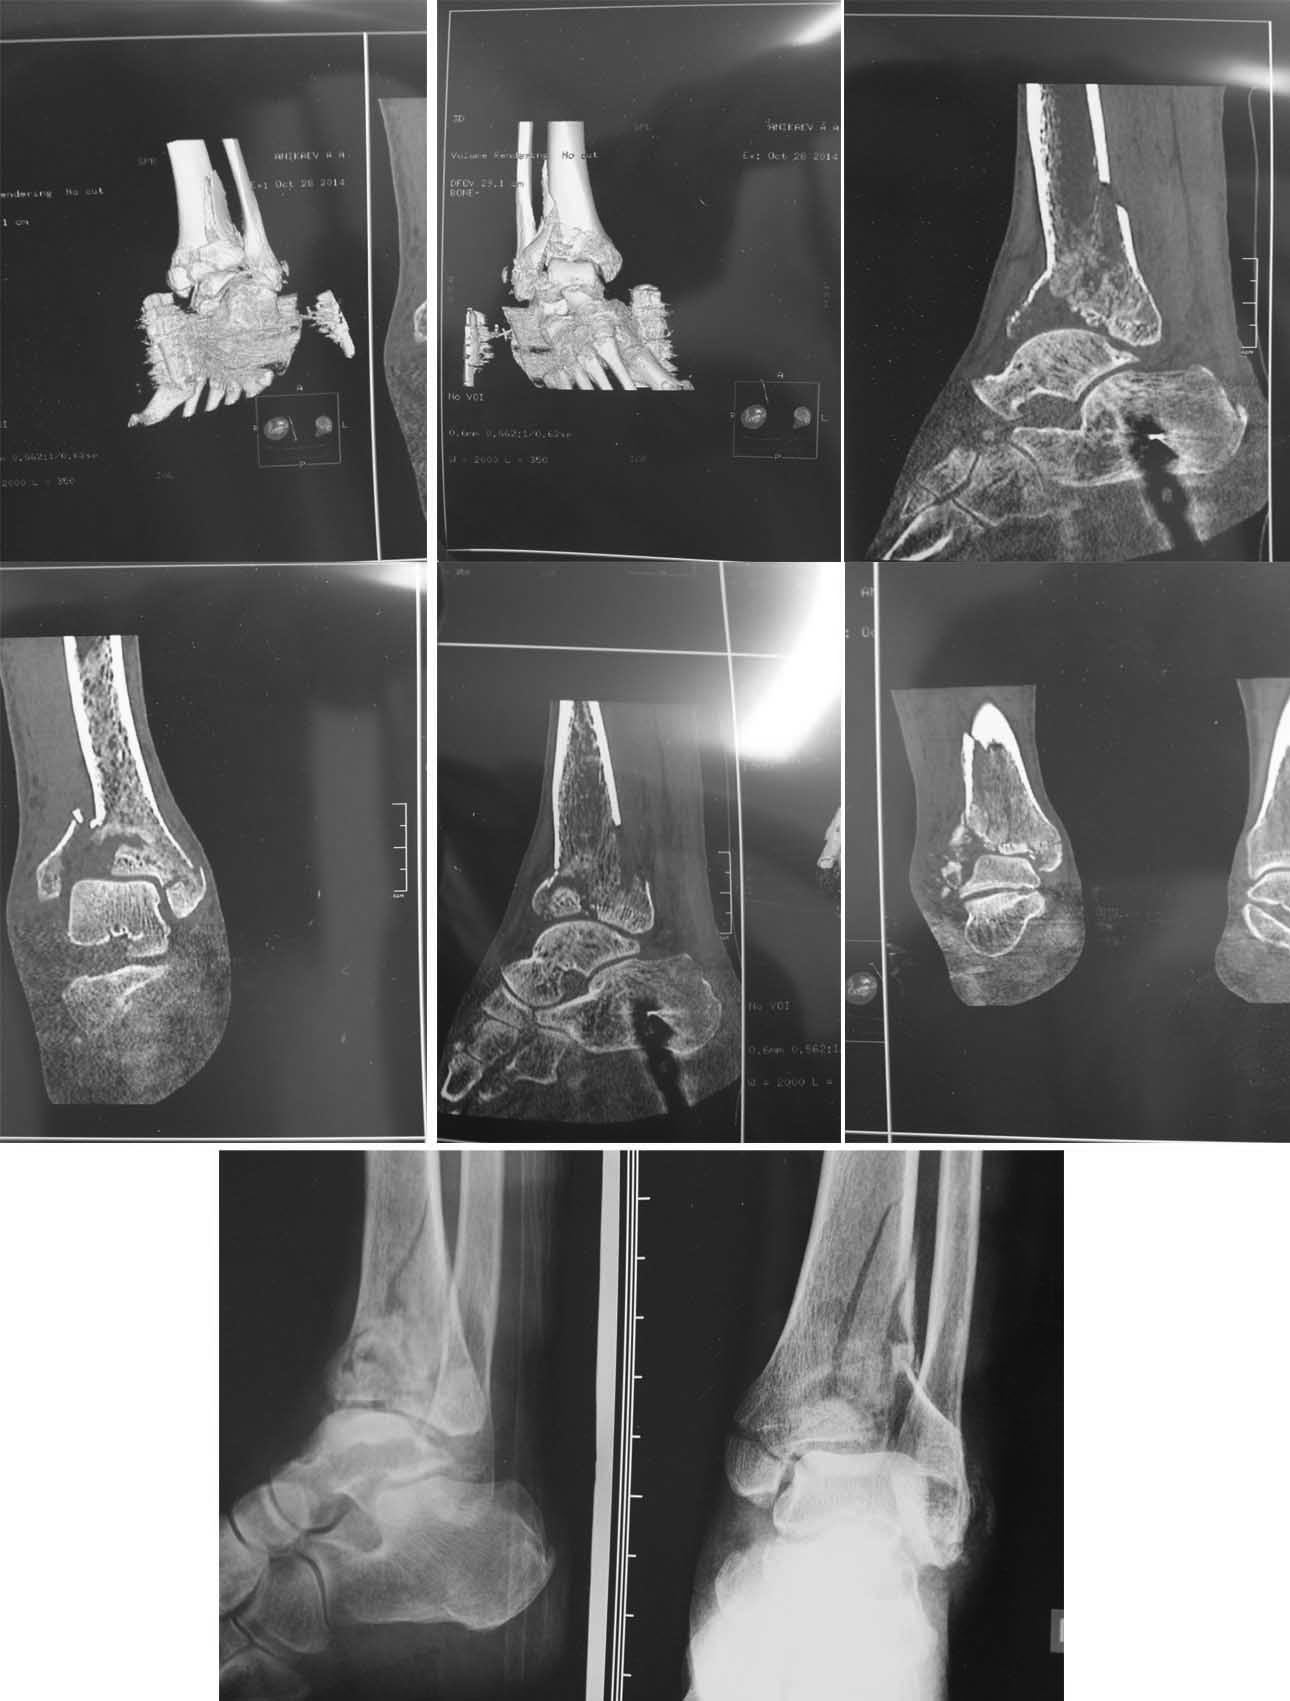

Добрый день, уважаемые коллеги! Мужчина 52 лет, упал с высоты трёх-четырёх метров 23.10.14. Закрытый перелом пилона.

Малоберцовая кость целая (на всём протяжении сделали Rg).При поступлении наложено скелетное вытяжение. Отёк, фликтены. Перевод скелетного вытяжения на дистрактор (спица в пяточной кости, спица в бугристости большеберцовой кости, полукольца, телескопические штанги). На данный момент: отёк купируется, фликтены заживают. Мужчина без вредных привычек, работает электриком-монтажником.

Смущает большой дефект по латеральной суставной поверхности большеберцовой кости.